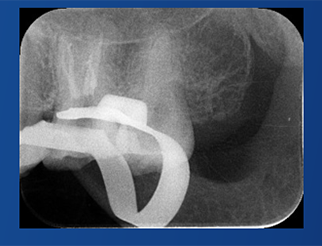

C-Root SP是預混合的、可即刻應用的、可注射的、遇水凝固的硅酸鹽類生物活性陶瓷糊劑材料,主要成分為硅酸鍶、氧化鋯、磷酸鈣、氫氧化鈣,用于根管的密封和永久充填,適合單尖法、側壓法和熱牙膠法。 C-Root SP為世界口腔醫生提供一個“鍶生物陶瓷”的新選擇! >>>